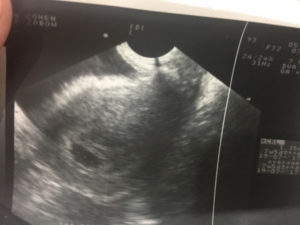

К этому времени матка уже начинает заметно (по крайней мере, для врача-ультрасонолога) увеличиваться относительно своего прежнего состояния, ведь внутри нее находится плодный пузырь диаметром более 1 см, что составляет примерно ¼-1/5 часть ее «добеременного» размера. Правда, на этом сроке увеличение часто происходит не равномерно, а асимметрично: стенка, к которой прикреплен пузырек с эмбрионом, приобретает выпуклость, а остальная часть органа пока что остается прежней.

При визуализации матки без увеличения пятинедельная беременность видна на экране в виде округлого или овального пузырька. Однако общая картина уже отличается от той, что специалист мог наблюдать, например, на 3 неделе. Меняется не только размер плодного яйца, но и его содержимое: внутри при увеличении изображения в несколько раз можно разглядеть желточный мешок и сам эмбрион.

На пятой неделе специалист-ультрасонолог уже отлично видит, что матка увеличилась. Но это увеличение пока может быть не совсем равномерным: так, может увеличиваться и стать выпуклой только стенка, на которой закрепился пузырек с эмбрионом.

Плодный пузырь уже видно отлично, его размеры составляют около сантиметра. Если же увеличить изображение плодного пузыря, то можно будет увидеть и сам плод, и желточный мешок. Хороший специалист способен распознать на УЗИ даже биение только формирующегося сердца плода.